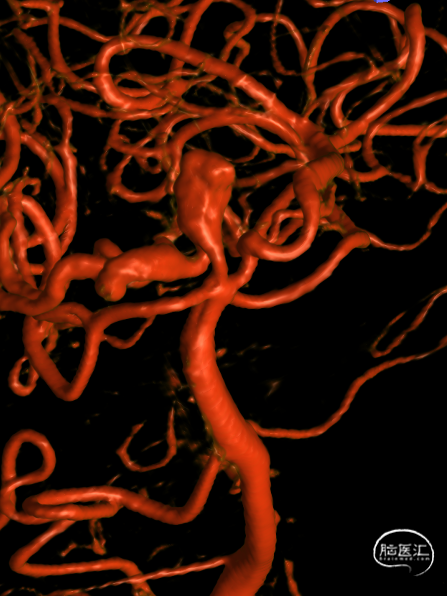

DSA:右侧P1段一6.8*9.7mm不规则囊状突起动脉瘤,远端P2段呈螺旋状蛇形动脉瘤改变。

DSA:右侧P1段一6.8*9.7mm不规则囊状突起动脉瘤,右侧A1段动脉瘤。夹层蛇形动脉瘤。

DSA:评估右侧后交通。

右侧颈内3D

椎动脉压颈3D

动脉瘤参数:

动脉瘤大小为6.8*9.7mm,瘤颈宽4mm

载瘤动脉(颈内动脉)近端狭窄处为1.7mm,近端末狭窄处为1.4mm,远端为2.4mm。